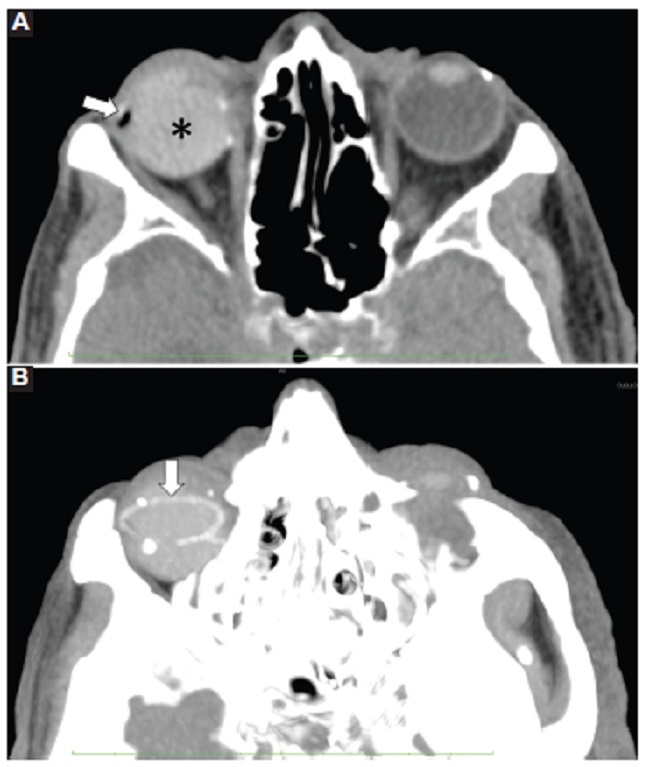

La rotura del globo ocular es una emergencia oftalmológica que puede llevar a complicaciones severas como endoftalmitis postraumática, pérdida de la visión y ceguera, oftalmía simpática, meningitis, abscesos cerebrales o incluso la muerte9,10.

Debido a que la rotura del globo ocular es una causa importante de ceguera, esta debe descartarse en los pacientes con trauma ocular. En los traumas contusos, los sitios de inserción de los músculos intraoculares son los sitios más comunes de rotura debido a que la esclera es más delgada en esta zona1.

El diagnóstico puede ser obvio al examen clínico, pero en los casos dudosos la TC es el examen de elección, con sensibilidad del 56 al 68% en la detección de roturas ocultas al examen físico1,6,9. Yuan et al. (9 reportaron que la TC en el diagnóstico de rotura del globo ocular tiene sensibilidad promedio del 76% y especificidad promedio del 85%. Gad et al. (9 reportaron que la TC tiene sensibilidad del 87% y especificidad del 97,33% para la detección de perforación anterior del globo ocular7.

Los hallazgos tomográficos de lesión abierta del globo ocular incluyen el cambio en el contorno del ojo, pérdida obvia de volumen (llanta desinflada), la discontinuidad escleral, y el aire y los cuerpos extraños intraoculares1,6 (Figs. 2, 3, 10, 11, 12). La profundidad de la cámara anterior puede aumentar y asociarse a desplazamiento posterior del cristalino por rotura en el segmento posterior1.